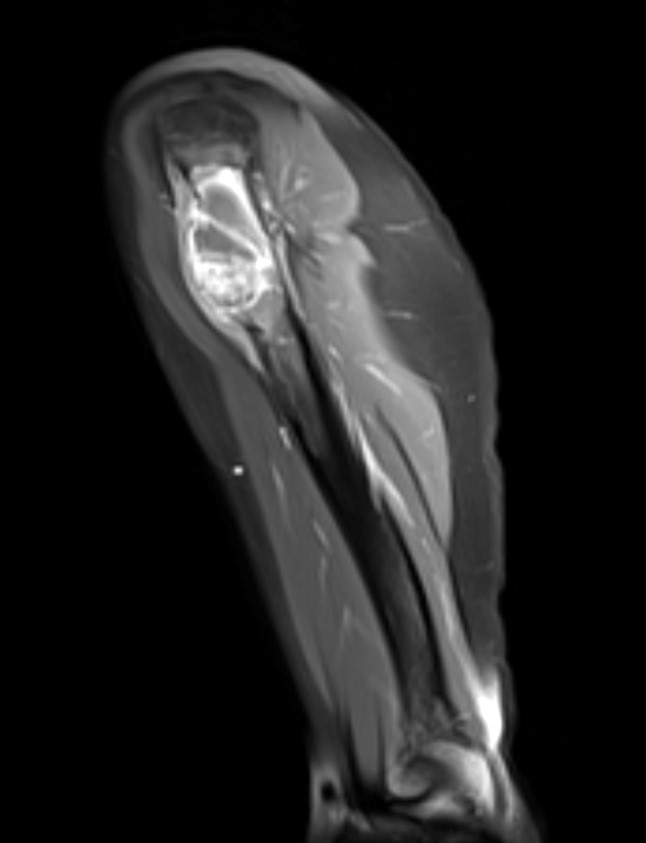

- Xray:

- Eccentric radiolucent lesion with expansile remodeling, involving the metaphysis of long bones

- Finger in the balloon sign possible (Orthop Traumatol Surg Res 2015;101:S119)

- CT scan:

- Well delineated lytic lesion, usually with thin rim of reactive bone

- Fluid-fluid levels occasionally visible

- MRI:

- Multiloculated cyst with characteristic fluid-fluid levels

- Isotope scan:

- Peripheral uptake with central photopenia imparts a donut-like appearances

Radiology images